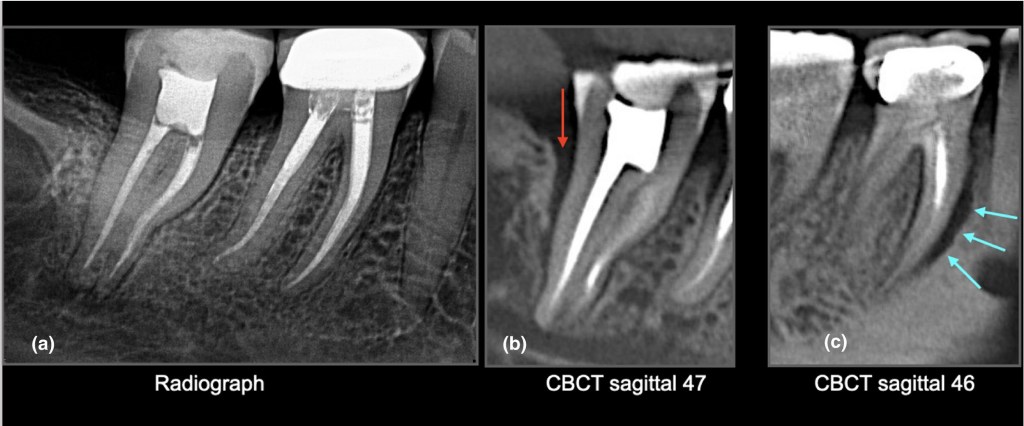

3️⃣ 植牙最怕的就是「過度咬力」

磨牙者的植牙承受壓力比一般人高很多:

• 螺絲鬆動

• 假牙破裂

• 植體周圍炎惡化

• 甚至植體本體鬆脫

都是臨床上很常見的問題。

戴咬合板能把過度咬力平均分散,大幅延長植牙使用年限。